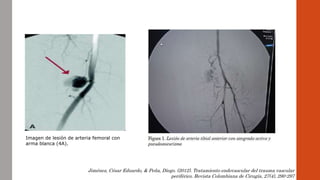

Imagen de lesión de arteria femoral con

arma blanca (4A).

Jiménez, César Eduardo, & Peña, Diego. (2012). Tratamiento endovascular del trauma vascular

periférico. Revista Colombiana de Cirugía, 27(4), 290-297

Imagen de lesiónde arteria femoral con arma blanca (4A). Jiménez, César Eduardo, & Peña, Diego. (2012). Tratamiento endovascular del trauma vascular periférico. Revista Colombiana de Cirugía, 27(4), 290-297